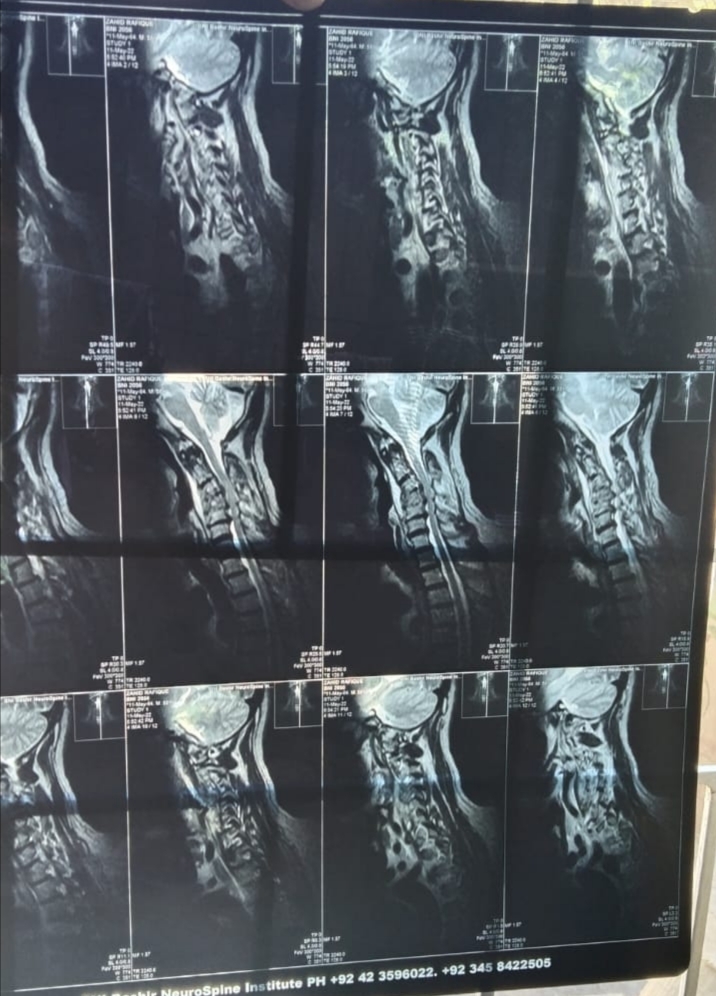

Asking for Brother, Male, 55 years old, lahore

patient is suffering from severe cervical pain and now there is limbs weakness dr said its tb drug didnt been a condition is getting worse day by any one give his/her can any one guide who can deal such case in lahore